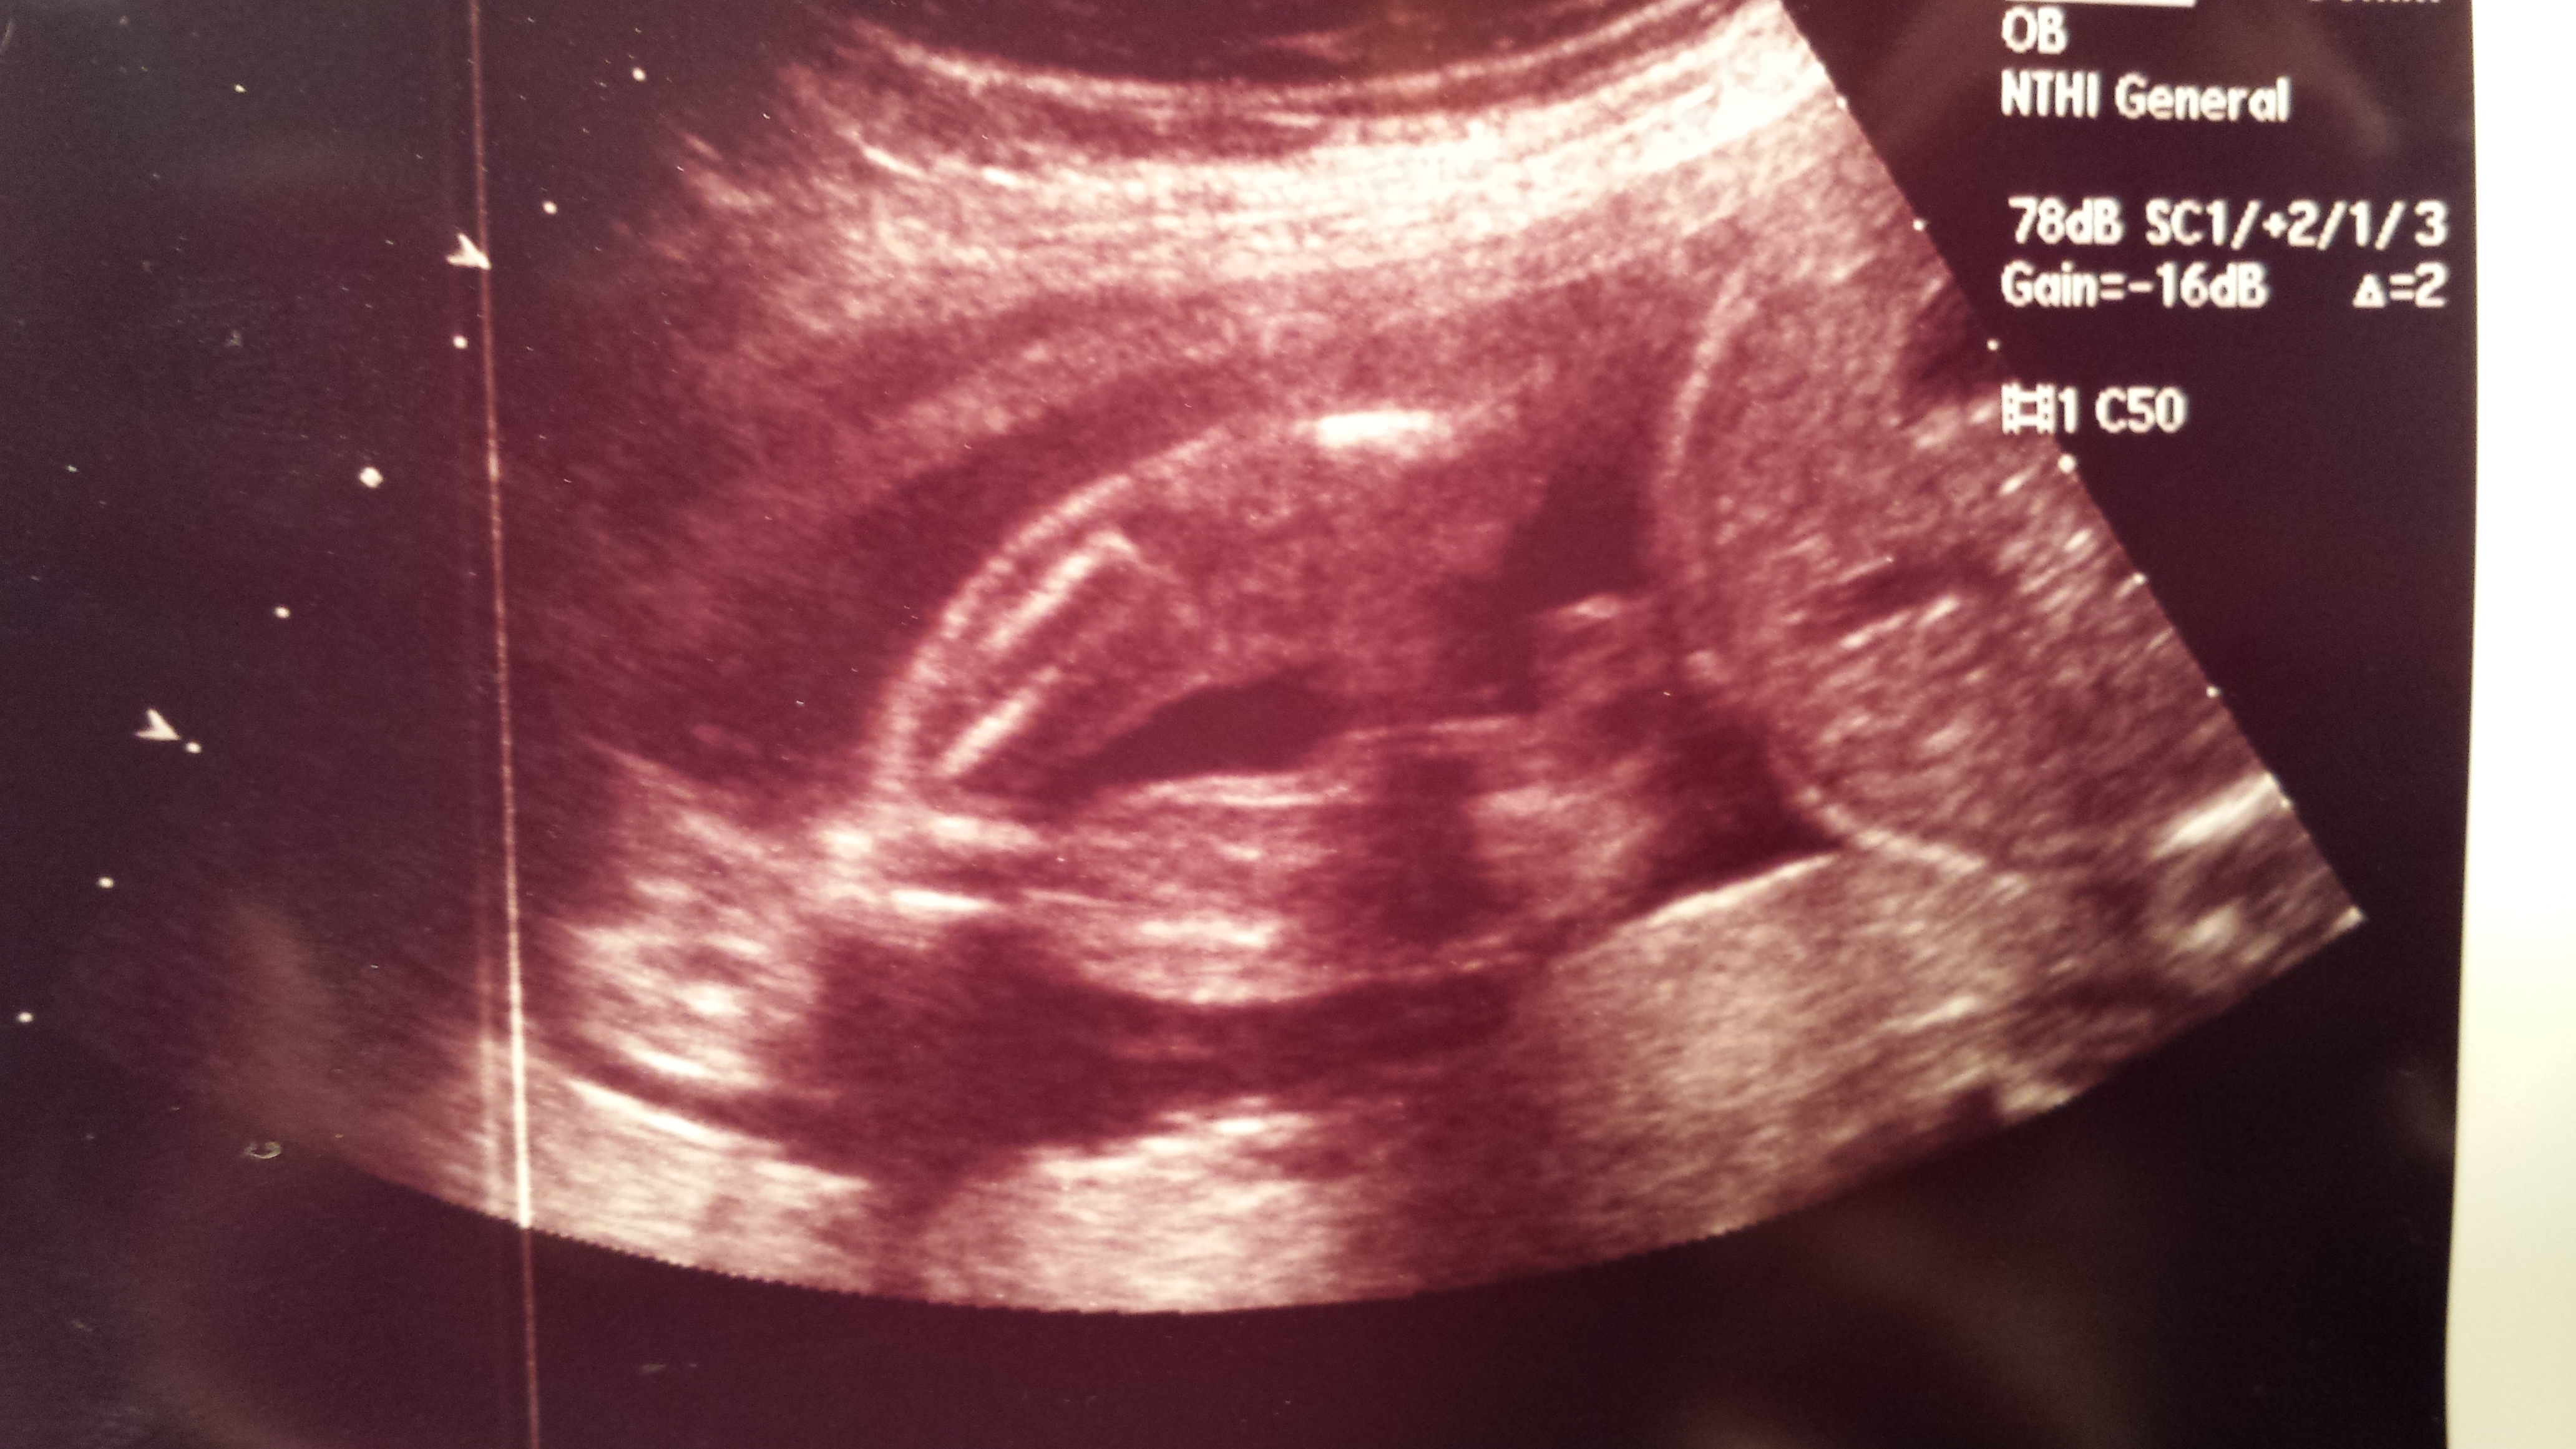

Attachment 20471 Crossed legs, but what do you think??? Boy or girl...

Looks like a boy

Can't guess on this pic